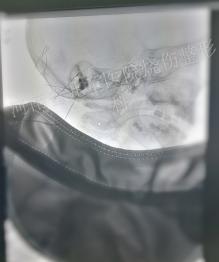

DSA下畸形血管团显影